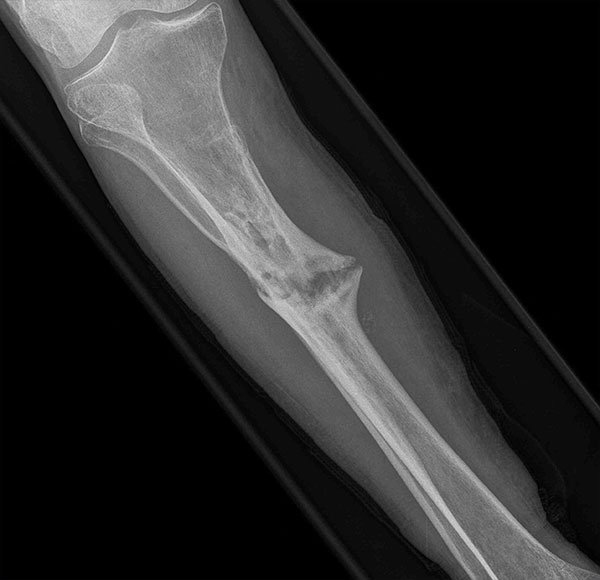

- Focus Area Reconstructive Surgery & Non-Surgical Management to Improve Bone Healing

- Sponsor DoD PRORP

- Primary Objective Observational study comparing outcomes following limb salvage versus amputation of a severe distal tibia, ankle, and/or foot trauma